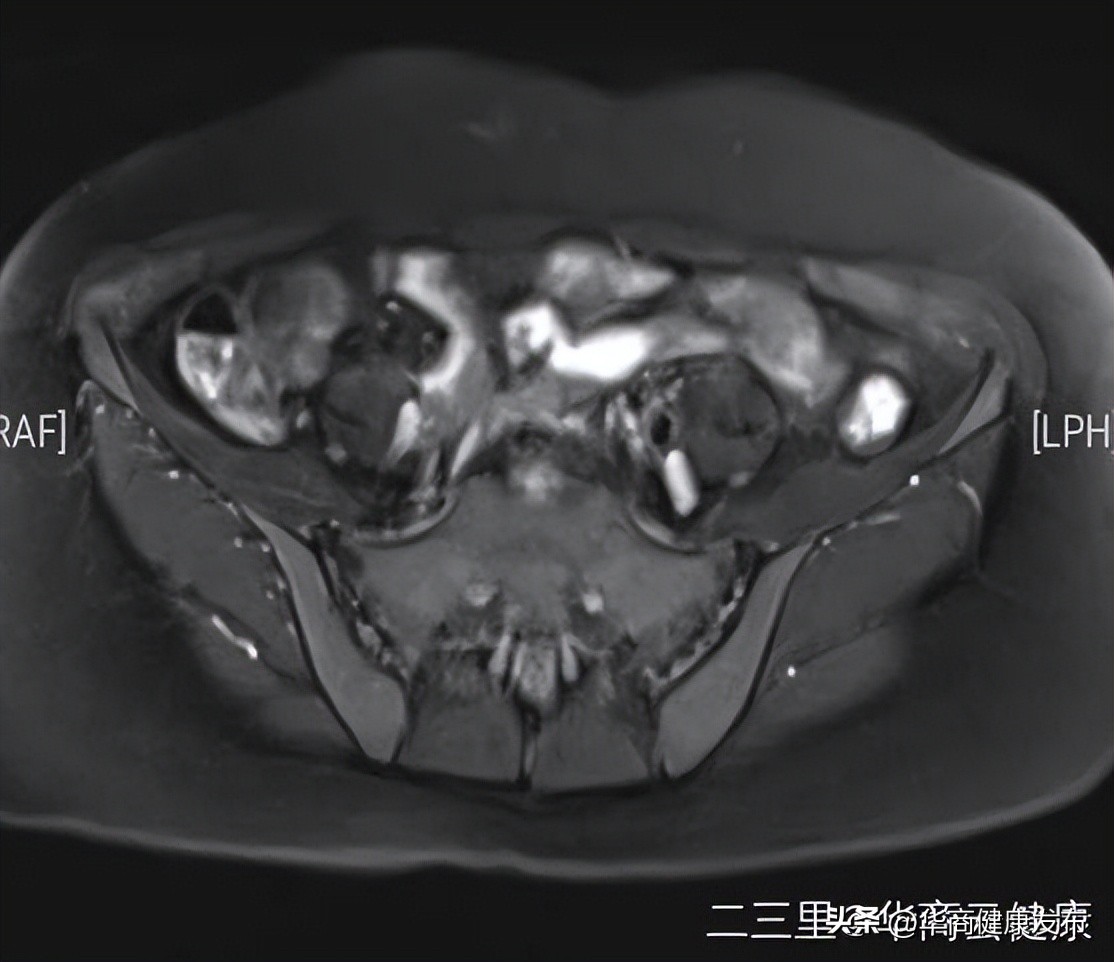

患者张女士,53岁,以“绝经3年,阴道不规则出血1月余”之主诉入院。妇科B超提示宫腔内有大小约3.1×1.5cm团块状低回声,其内可见血流信号延续于子宫后壁。身高126cm,体重50kg,BMI31.49。完善相关检查,盆腔MR提示子宫内膜病变,累及深肌层。

宫腔镜检查+内膜病检考虑子宫内膜恶性肿瘤;患者体型肥胖,多学科协作下,妇三科主任医师邱育红及刘亚红副主任医师团队为患者行微创腹腔镜下子宫内膜癌全面分期手术治疗(腹腔镜筋膜外全子宫+双附件切除+盆腔淋巴结切除+腹主动脉旁淋巴结切除术),手术成功,拟行后续放化疗及基因靶向治疗。通过此案例分享,呼吁广大女性重视绝经后出血,预防子宫肿瘤。